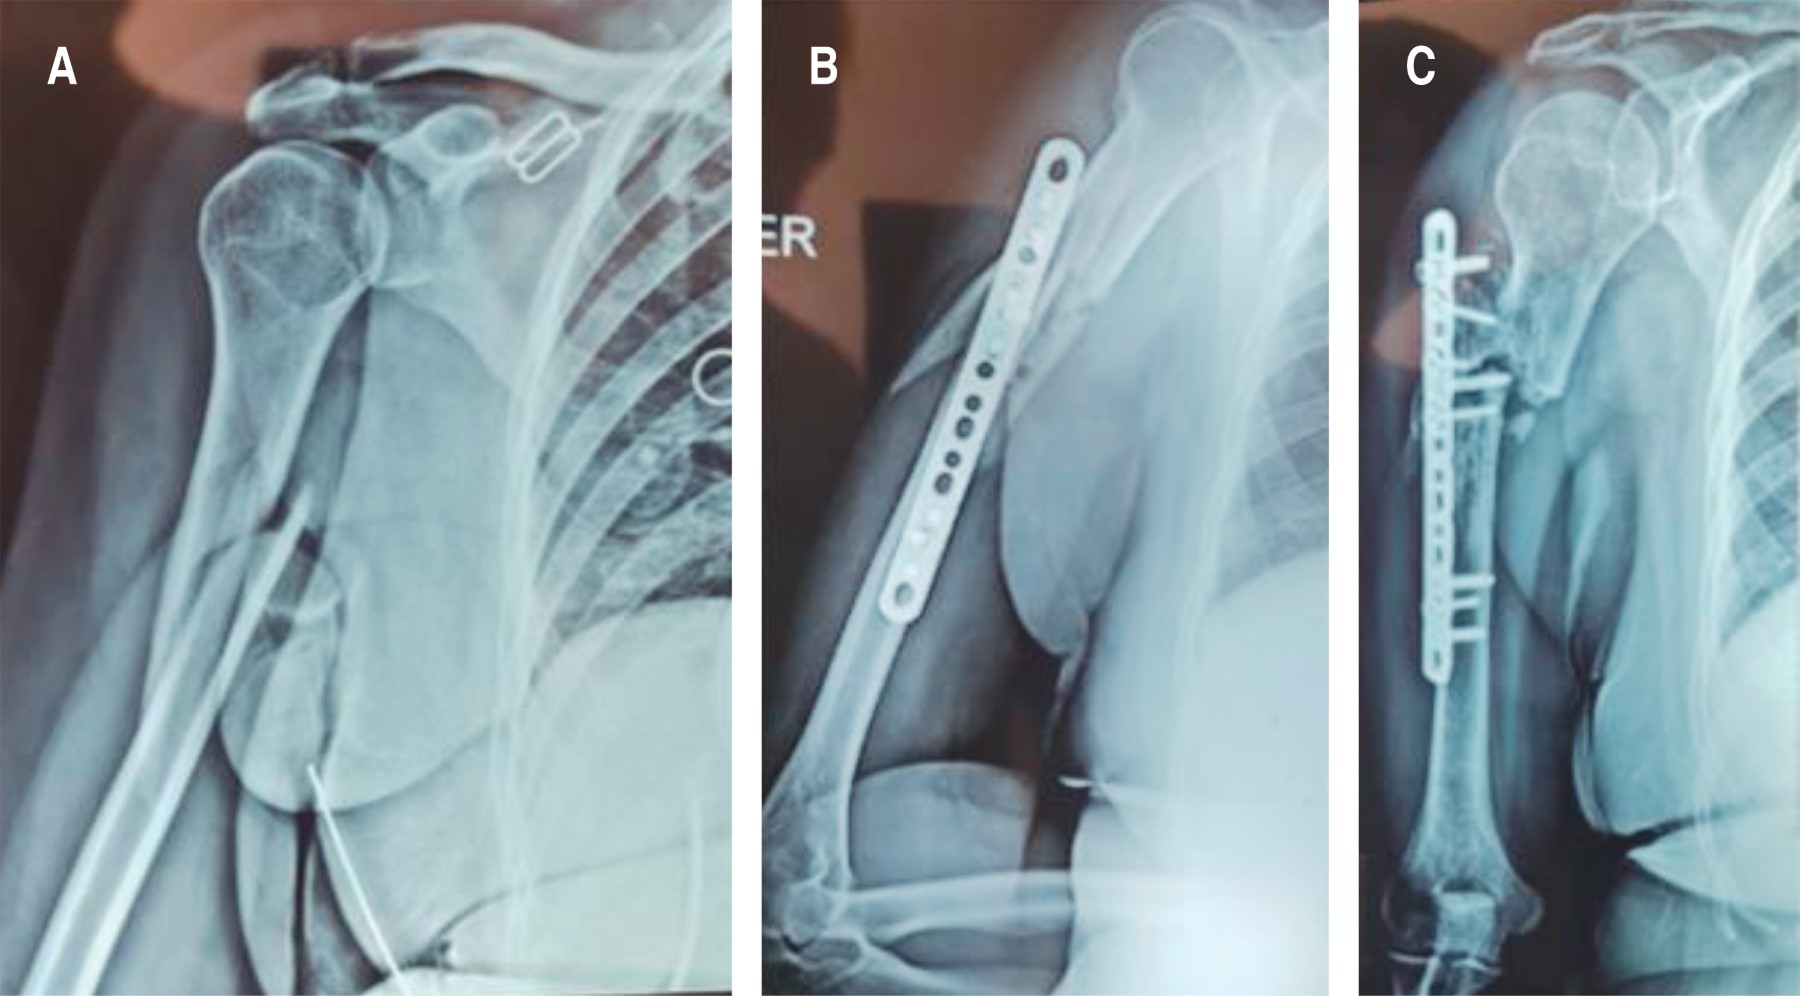

Introduction: different techniques have been described for the treatment of nonunion. However, there are very few reports on the use of autologous tricortical iliac crest graft. The objective of reporting this case is to emphasize the importance of using the autologous tricortical iliac crest graft, in the context of the "diamond concept", after 3 failed surgeries for humerus nonunion. Case report: female, 69 years old, type 2 diabetes mellitus, grade III obesity, diagnosis of aseptic oligotrophic nonunion of the right humerus plus radial nerve injury, underwent 3 previous surgeries without success in resolution. The treatment consisted of performing osteosynthesis with an locking compression plate (LCP) for the proximal humerus and application of the "diamond concept" through the use of autologous tricortical iliac crest graft, bone marrow aspirate, platelet-rich plasma and demineralized bone matrix, as well as exploration and decompression of the radial nerve, achieving complete consolidation and functional recovery. Conclusion: after 3 failed surgeries, and after a bone loss of 7 cm, complete bone consolidation and full functional recovery are achieved through the application of the "diamond concept" with the complement of the use of autologous tricortical iliac crest graft.

Figure 2